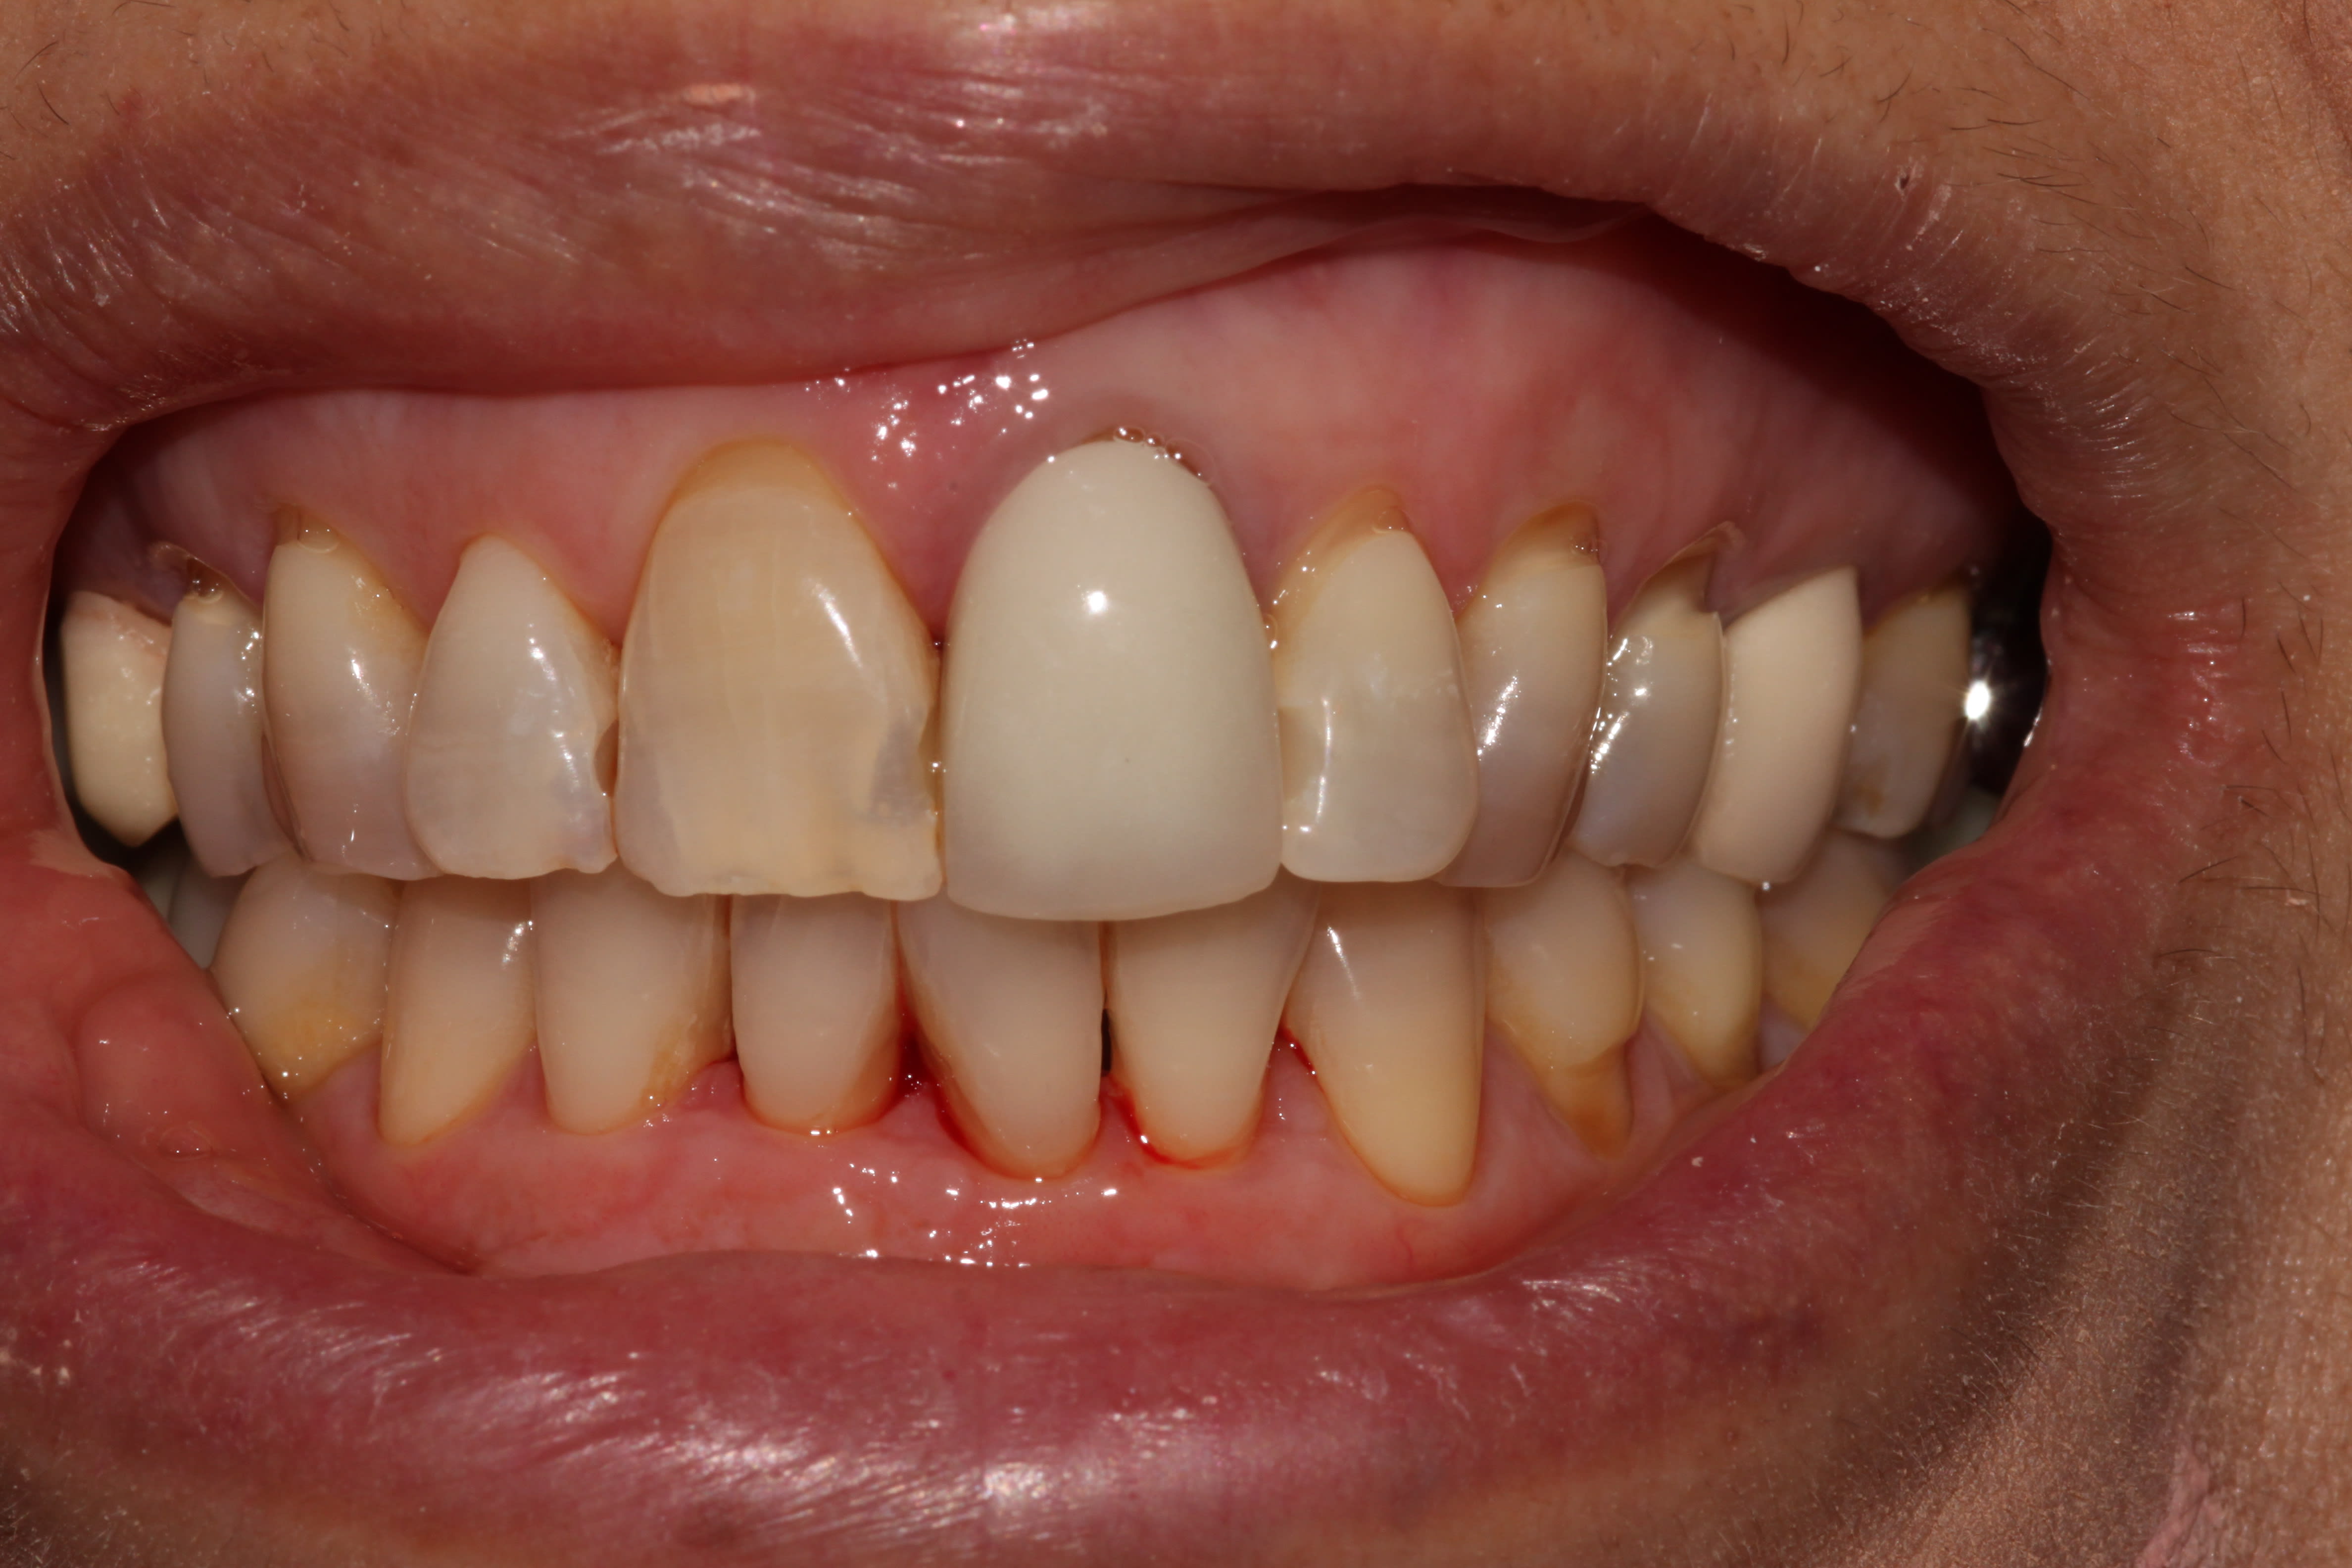

27/05/2019 à 18h54

Conventionné bien sûr.

Mais juste pour faire comprendre l'état d'esprit.

Patiente polycariée suivie en 2014 je crois, je fais plein de compos juxta pulpaires, consigne de contrôle à 6 mois.

Je la revois en 2019, 15 min en urgence pour un accident d'évolution de dds, pano ce jour. Aujourd'hui, 45 min prévues (30 en réel) pour faire le compo, un sillon à l'amalgame sur 17 et le détartrage.

En tout, une heure de temps prévu, plus ou moins 150 balles de CA et le temps de boire mon café en post prandial. Je suis en mode détente.

De toute manière, ce n'est pas ça qui me fait croûter, donc pourquoi chercher à gratter 5 minutes en bourrinant? Tu vois l'idée?